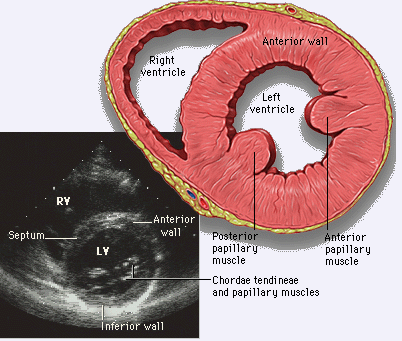

5.胸骨旁腱索水平短轴切面

1)正常结构的超声心动图表现:图右侧依次显示左室前壁、侧壁、后壁,中部为室间隔。右前方为右室前壁、右室腔及右室后壁。

2)此切面选用范围:

①测量左室腔径(前后及左右径),评价左室大小,观察左室壁厚度及室腔形态(正常左室腔呈圆形),腔内显示乳头肌上缘或键索。

②右室腔大小、位置及形态,有无扩大、转位。

3)正常测值:左室横径舒张末期为3.3-5.3cm ,收缩末期为2.4-4.2cm。

胸骨旁腱索水平短轴切面

Relationship between the short-axis plane with left ventricular wall segments indicated, and the apical four-chamber, two-chamber, and long-axis image planes (perpendicular to the short-axis plane).